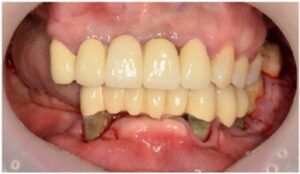

최종 보철물은

자연치아와 강도가 유사하고

심미적인 지르코니아 보철물로

마무리해 드렸습니다.

모든 치료가 마무리된

파노라마 사진과

구강 내 사진인데요.

환자분께서는

치료 후 양측 저작이 편안해지고

심미적으로 변한 모습에

만족해하셨습니다.